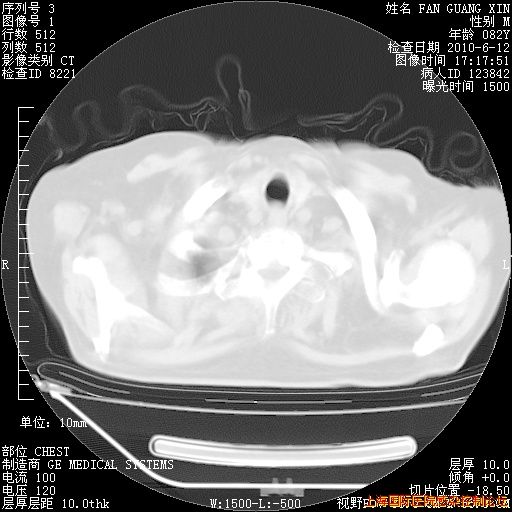

6月12日纵膈窗